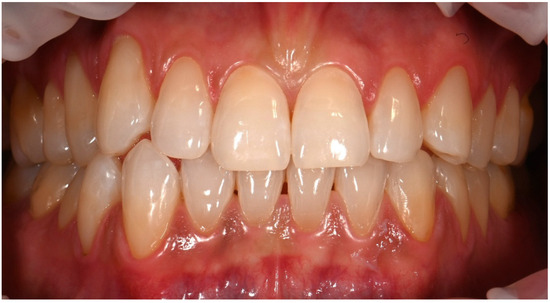

Clinical Management of Cervical Restorations with Closing Gap Technique: A Follow-Up of Two Cases

Background: Cervical restorations remain clinically challenging due to complex anatomy, limited enamel availability, and difficulties in achieving reliable adhesion at dentin or cementum margins. Polymerization shrinkage and marginal leakage are frequent causes of failure. Although the Closing Gap Technique has been proposed to [...] Read more.

Background: Cervical restorations remain clinically challenging due to complex anatomy, limited enamel availability, and difficulties in achieving reliable adhesion at dentin or cementum margins. Polymerization shrinkage and marginal leakage are frequent causes of failure. Although the Closing Gap Technique has been proposed to improve marginal adaptation in cervical restorations, evidence supporting its medium- to long-term clinical performance is limited. The aim of this case report was to evaluate the clinical effectiveness of the Closing Gap Technique in the restoration of carious and non-carious cervical lesions. Materials and Methods: Two patients presenting with cervical lesions were treated using the Closing Gap Technique. One case involved carious cervical lesions, while the second included multiple non-carious cervical lesions. Restorations were performed following an enamel-anchored incremental layering protocol with resin composite. Clinical evaluations were conducted at 8 years (case #1) and 2 years (case #2) post-treatment, respectively. Results: Both cases demonstrated favorable clinical outcomes at follow-up. The restorations exhibited good marginal integrity, satisfactory esthetics, absence of marginal discoloration, no secondary caries, and no signs of debonding. The only minor defect observed was slight chipping of one of the restorations. Conclusions: Within the limitations of this case report, the Closing Gap Technique showed stable and predictable medium- and long-term clinical performance, supporting its use as a viable restorative approach for managing cervical lesions in daily clinical practice. Full article